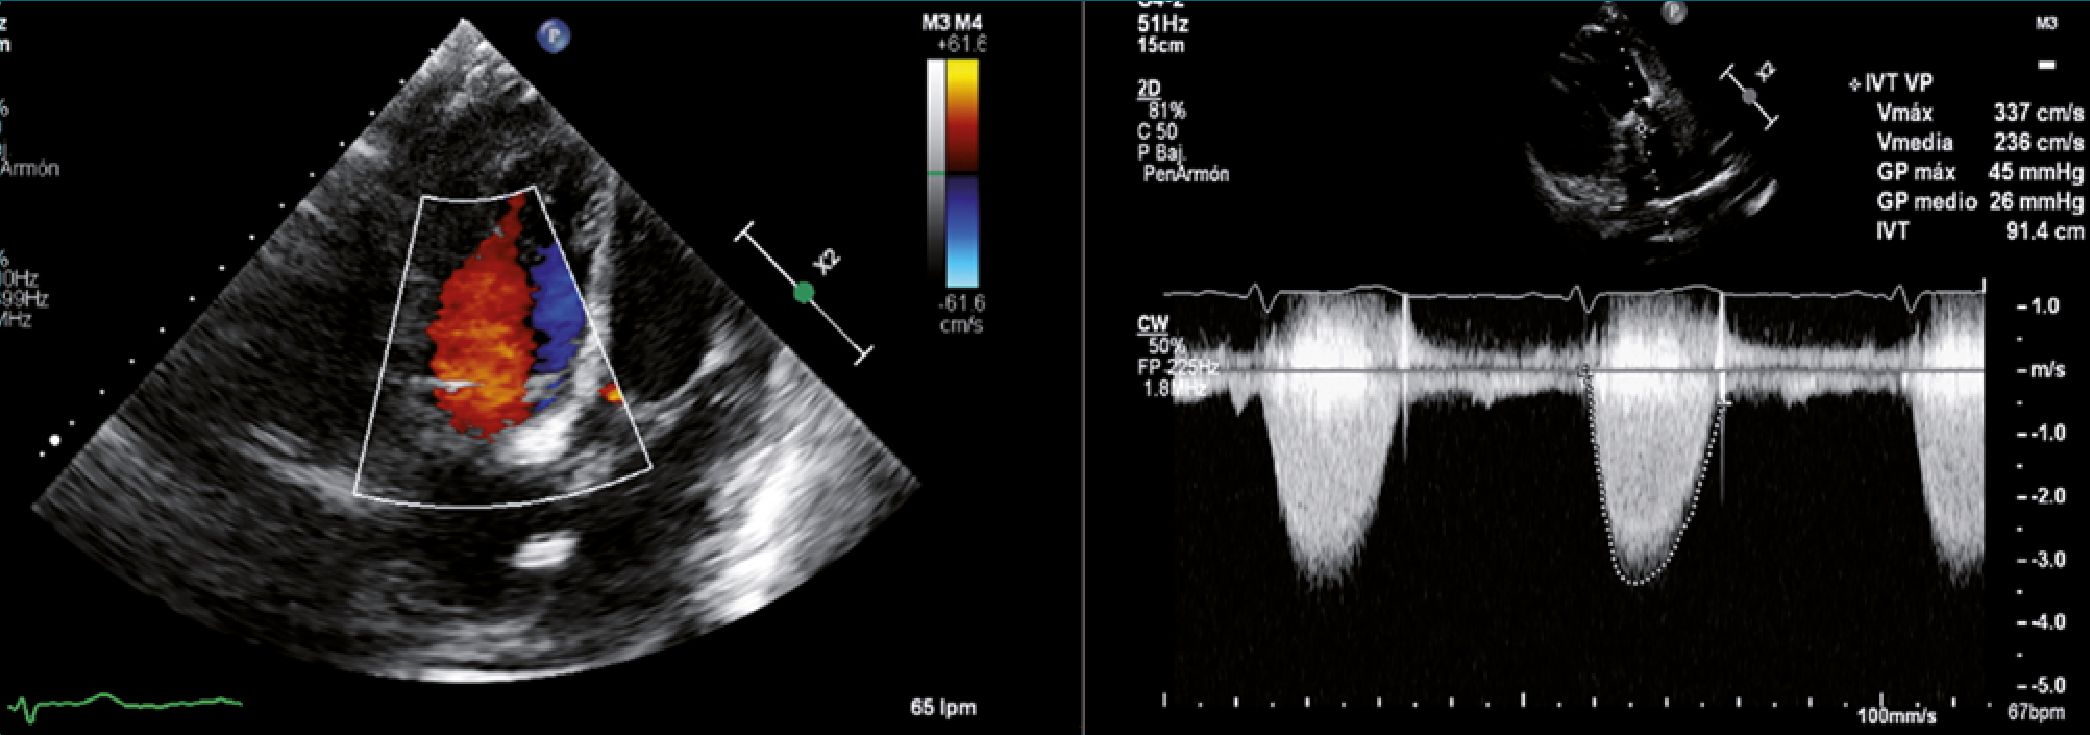

El paciente fue traslado a la unidad de cuidados intensivos con vasopresina 4 UI/h, dobutamina 5 mcg/kg/min, adrenalina 0,1 mcg/kg/min y azul de metileno 0,5 mg/kg/h. Fue desempaquetado a las 48 h con extubación exitosa. Se logró el destete del soporte vasopresor e inotrópico. Se suspendió infusión de octreotide 100 mcg/h a las 72 h posoperatorias. No presentó crisis carcinoide perioperatoria ni otras complicaciones durante la estancia en UCI. Traslado a piso de hospitalización a los 7 días con ECOTT FEVI 60%, ventrículo derecho con función sistólica levemente deprimida, prótesis biológicas sin parafugas y patrón Doppler color normal (Figura 3 A y B).

Figura 3. A y B. A: ECG TT plano apical 4 cámaras. Prótesis biológica en posición tricúspide con Doppler color que descarta fugas para valvulares, sin evidencia de insuficiencia transprotésica; B: ECG TT plano transversal grandes vasos. Doppler continuo a nivel de la bioprótesis pulmonar que permite calcular un Gradiente pico 45 mmHg, Gradiente medio: 26 mmHg, velocidad Max 3,36 ms/s considerándose prótesis biológica normo funcionante.